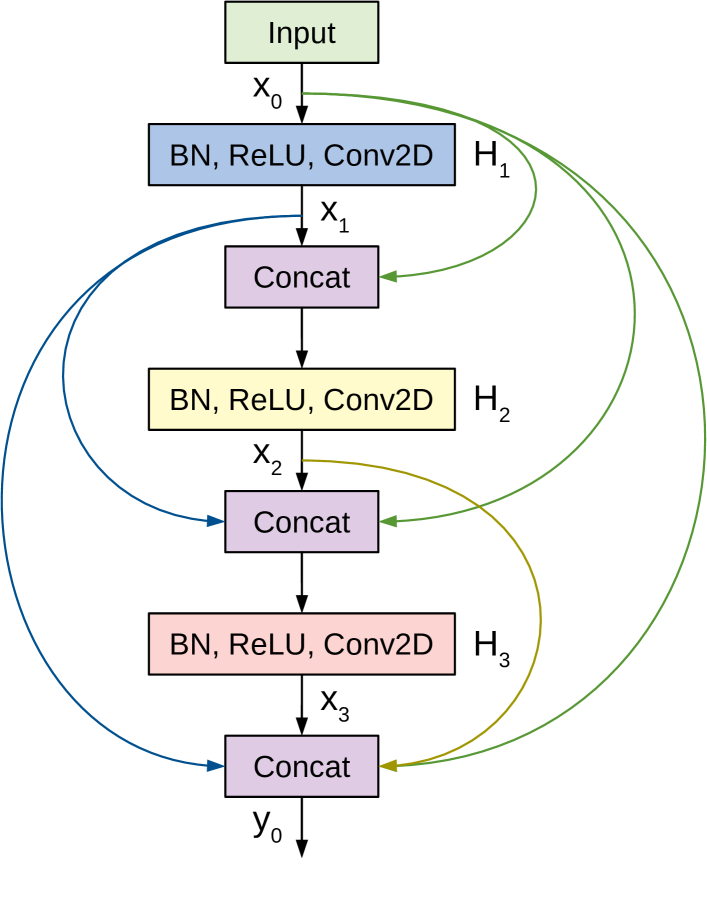

3.7 DenseNet

Densely Connected Convolutional Networks (DenseNets) are a class of CNN architectures introduced in [44] with several compelling characteristics. They alleviate the vanishing gradients problem, foster feature reuse, achieve high performance, consolidate feature propagation, and are computationally efficient. DenseNets modify the shortcut connections from ResNet by concatenating the output of the convolutions instead of summing them up. So, the input to the next layer will be the feature maps of all the preceding layers.

Figure 6 shows a 3-layer Dense block where each layer performs a set of batch normalization (BN), ReLU activation and Convolution operations. Previous feature maps are concatenated and presented as the input to a layer, which then generates feature maps. is a newly introduced hyper-parameter, denoted as the growth rate. Thus, if the input to layer is , then the number of feature maps at the end of a 3-layer Dense block is . To prevent the number of feature maps from increasing too rapidly, DenseNet introduces a bottleneck layer with convolution and filters. To tackle the difference in the feature map sizes when transitioning from a large feature map to a smaller one, DenseNet applies a transition layer made of convolution and average pooling.

A deep DenseNet is constructed by stacking multiple Dense blocks with transition layers. Conventional convolution and pooling layers are used at the beginning of the network. Eventually the output is pooled by Global average pooling, flattened and passed to a softmax classifier. For our study we experiment with three variants of DenseNet, the 121-layer, 169-layer and 201-layer architectures. The original models use an RGB-input of , however, we found that an input size of achieves better results for images from the used datasets.